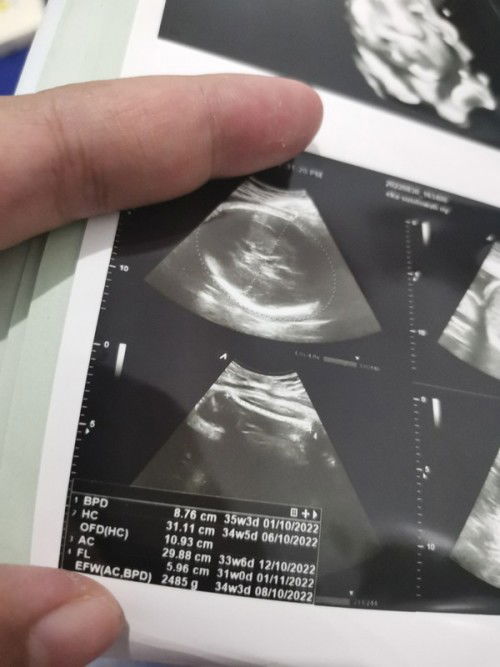

Usia di hasil usg beda2

Mau nanya ada yg tau ga knp parameter yg diukur di USG, usia nya beda2. Klo menurut foto usg brarti kaki anak ku lbh kecil ya... Soalnya usianya jauh dr parameter lain. Aku udh minum kalsium dr usia 5bln. Tp ttp aja selalu FL nya beda jauh dr usia yg lain. Adavyg punya pengalaman sama ga...